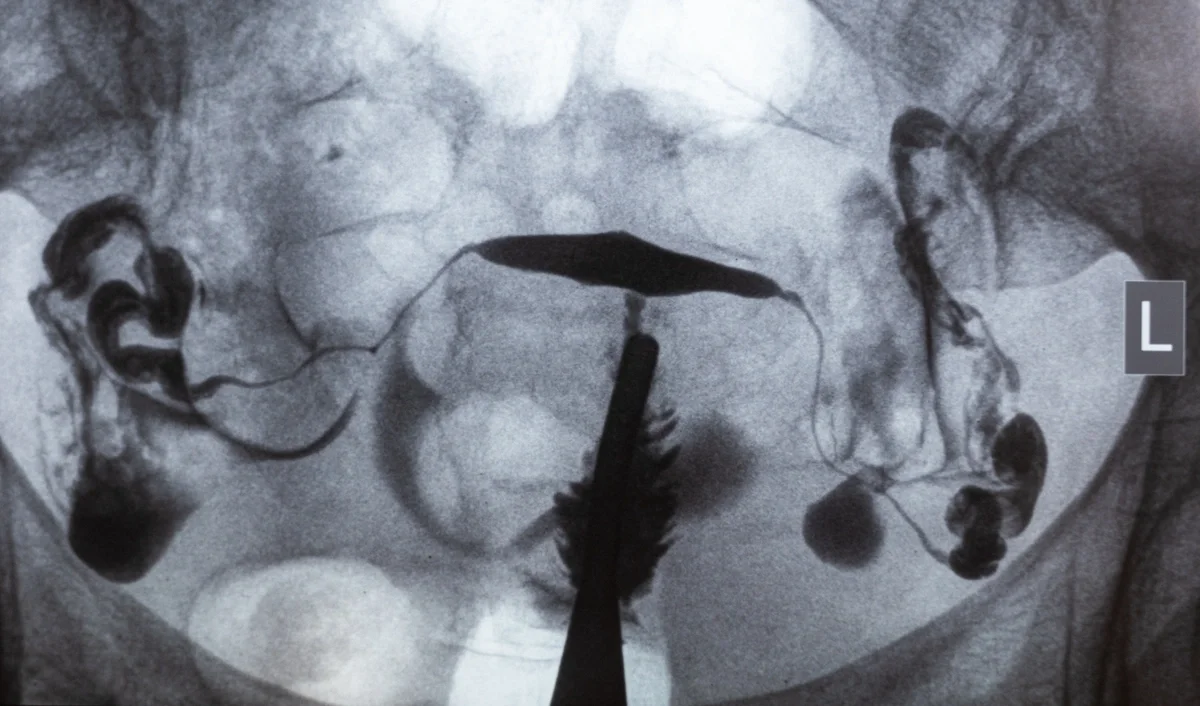

• Hysterosalpingogram (HSG): This X-ray procedure uses a contrast dye injected into the uterus and fallopian tubes. If the dye flows freely, the tubes are open; if not, a blockage is present. While HSG can cause mild cramping, it provides valuable insight into tubal health.

undefined

X-ray image of HSG